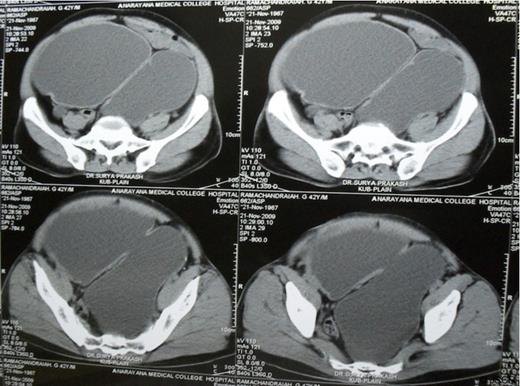

Cystoscopy showed a normal urethra, a solitary, large, wide mouthed diverticulum arising from the left posterolateral wall of the bladder and left ureteric orifice was not visualised. In view of non functioning left kidney and large bladder diverticulum with chronic urinary retention, left nephroureterectomy and diverticulectomy was carried out. Macroscopic examination of the specimen revealed that the left kidney was grossly dilated with a thinned out parenchyma and a dilated left ureter entering into the diverticulum (Fig. 2). Diverticulectomy was undertaken using a combined intravesical and extravesical approach. The patient made an uneventful recovery

Left nephroureterectomy and bladder diverticulectomy specimen with Left ureter opening into the diverticulum